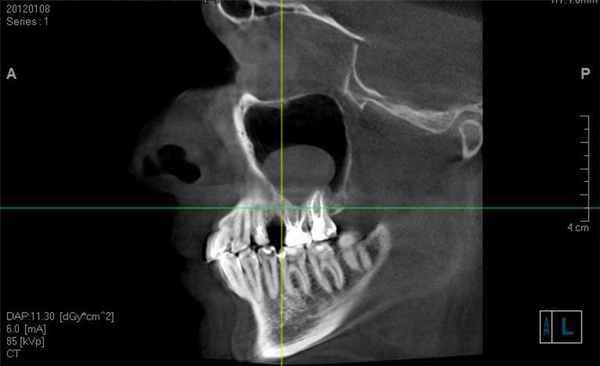

На рентгеновском снимке о наличии кисты можно говорить в случае, если в проекции пазухи имеется затемнение с краем, который может являться частью круга. Центр данного круга должен при этом находиться внутри пазухи, а не за ее пределами – в таких случаях речь идет, скорее, о наличии жидкости в пазухе (вязкого характера) или об ином экссудативном процессе. На рентгенограммах пазух кисты могут давать и картину тотального затемнения пазухи – в этом случае необходима дифференциальная диагностика с экссудативным гайморитом, муко- и пиоцеле, опухолью и т. д. На рентгенограмме определяются кисты верхнечелюстных пазух с обеих сторон. Обратите внимание на верхний край затемнения в пазухах – он ровный, имеет полукруглую форму, характерный для кист вид. В данном случае с целью уточнения размеров и локализации кист необходима компьютерная томография околоносовых пазух. Характерная для кисты верхнечелюстной пазухи картина при компьютерной томографии: обратите внимание на объемное образование в правой гайморовой пазухе, которое имеет ровные, закругленные края (отмечены стрелкой красного цвета), однородную структуру и плотность, соответствующую жидкости (+5…+15 единиц по шкале Хаунсфилда). Видно также, что выводной проток пазухи сужен, слизистая ячеек этмоидальной пазухи с правой стороны утолщена, имеет место утолщение слизистой носа – все это признаки катарального этмоидита, ринита, возникшего вследствие нарушения мукоцилиарного клиренса. Не путайте кисту верхнечелюстной пазухи с пролабирующим в полость пазухи корнем зуба (отмечен стрелкой) – на рентгенограммах очень часто тень зуба дает картину, имитирующую кистозное образование в пазухе – зачастую только с помощью КТ пазух можно различить эти два состояния. На данных изображениях также представлена киста гайморовой пазухи справа – обратите внимание на аксиальный срез (слева). Только по одному аксиальному срезу сложно сделать вывод о том, что за образование находится в полости пазухи, однако при выполнении реформаций в сагиттальной плоскости можно убедиться, что это именно киста большого размера (по характерному для кисты ровному закругленному краю, отмеченному стрелкой). Также на изображении справа видно, что слизистая оболочка гайморовой пазухи справа утолщена, а в ячейках решетчатой кости с этой же стороны визуализируется содержимое в большом количестве, выводные протоки гайморовой и этмоидальной пазух не прослеживаются. В данном случае наличие большой кисты в гайморовой пазухе спровоцировало развитие воспалительной реакции слизистой и явилось причиной правостороннего этмоидита. На изображениях можно проследить следующую патологию – часть этмоидальной пазухи пролабирует в полость носа (пролабирующая ячейка заполнена содержимым жидкостного – исходя из ее плотности – характера; отмечена стрелкой). Утолщена также слизистая верхнечелюстных пазух, резко сужены их выводные протоки (отмечены цифрой 1 на левом скане). На изображениях в аксиальной плоскости (слева), сагиттальной (в центре) и корональной (справа) плоскостях видна киста правой гайморовой пазухи. На КТ она выглядит как образование с ровными краями, жидкостной плотности (обозначена на всех сканах красными стрелками). На крайнем правом скане также цифрой 1 обозначена правая половина этмоидальной пазухи, заполненная содержимым. Имеются также признаки катарального гайморита (на левом скане) – оцените слизистую оболочку левой гайморовой пазухи – она явно утолщена. Небольшая киста гайморовой пазухи на КТ справа. Отмечена стрелками. Располагается пристеночно у задних отделов медиальной стенки и нижней стенки пазухи. Не вызывает нарушений отхождения слизистого секрета из пазухи.